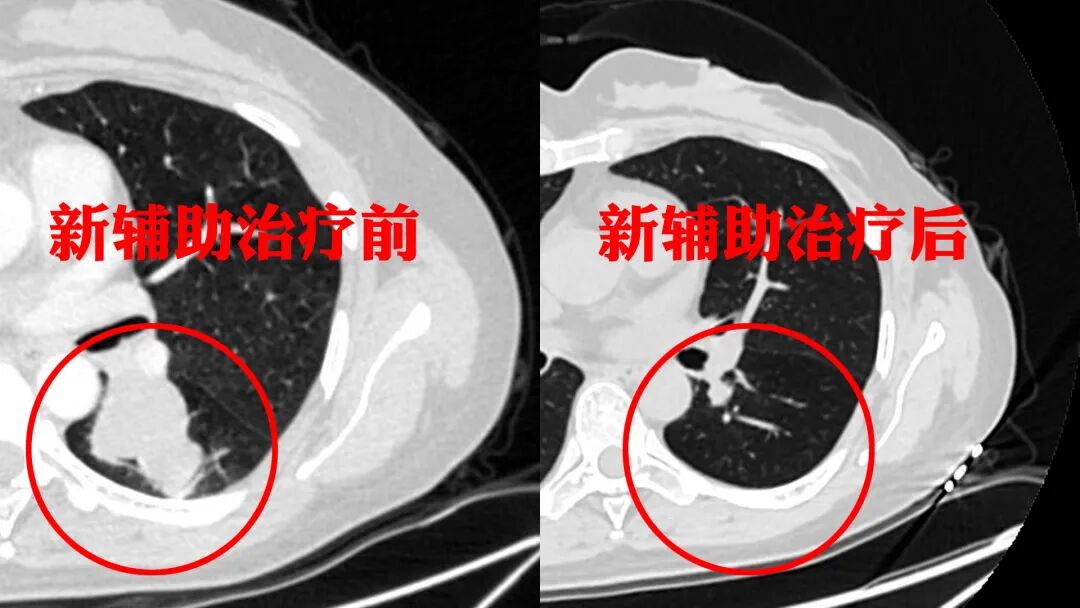

“各项指标都很正常,恢复得很好!”烈日炎炎下的门诊,患者刘女士前来进行术后复查。她气色红润、笑容灿烂,丝毫看不出一个月前曾与“癌魔”积极抗争。我院胸外科、呼吸内科内外科联合,默契协作、精准施策,通过“新辅助治疗+单孔胸腔镜手术”方式,以最小的创伤,为刘女士“消灭”了肺里近5公分的肿瘤。来时尚是寒冬,转眼已入酷夏,治好了病,夫妻两终于踏上了回家的路。 新辅助治疗前后CT图对比 “发现肿块时已经很大了,好多专家都说要开胸把左肺全切了……”今年49岁的刘女士被诊断为左肺中央型肺癌,咨询了当地多家医院,都建议做开胸大手术。然而刘女士还年轻,摘除左肺必将影响今后的生活质量。一家人心有不甘,多方打听下来到我院求助。胸外科副主任医师仲晨曦接诊了刘女士。经过内外科联合会诊及细致评估,医生们为她制定了新辅助治疗后再手术的治疗方案。该方案能够提高根治性切除肿瘤的可能性,让患者有更好的远期疗效。 呼吸内科副主任医师钟润波先为患者进行了新辅助化疗及免疫治疗。当时虽受疫情影响,团队仍克服重重困难,密切关注患者病情,及时调整用药方案。经过两个疗程的治疗,效果很好!刘女士的肿块缩小至只有1.5公分!手术的时机到了。仲晨曦医生施行了单孔胸腔镜下左肺下叶支气管袖型切除术,在3厘米的微创切口下切除肿瘤、缝合支气管、清扫淋巴结一气呵成,在根治性切除肿瘤的同时也保留了更多的健康肺组织,避免了全肺切除,让她获得更好的预后和生活质量。术后,刘女士康复得很快,没几天就出院了。 新辅助化疗加免疫治疗,给刘女士带来了很好的疗效,为其手术开展创造良好条件,这到底是一种怎样的治疗模式,听听我们专家的介绍。 什么是新辅助治疗? 新辅助治疗是相对传统的辅助治疗而言。传统的辅助治疗是指在手术后进行的治疗,如放疗、化疗,而新辅助治疗是指在手术前进行的,包括放疗、化疗、免疫治疗、分子靶向治疗、免疫联合化疗等,因此也可称为术前治疗。 哪些患者需要做新辅助治疗? 并不是所有患者都需要做新辅助治疗。目前临床上主要针对局部晚期可手术或者潜在可手术(II到III期的非小细胞肺癌)患者进行新辅助治疗,早期患者无需新辅助治疗,可以直接进行手术。 新辅助治疗的优势? 通过新辅助治疗,能够使肿瘤萎缩,降低肿瘤活性,为手术创造更好的条件,提高根治性切除肿瘤的可能性,让患者获得更优的整体疗效。另外,新辅助治疗还可以针对肉眼看不见的病灶进行治疗,把它们扼杀在萌芽状态。 什么是单孔胸腔镜下支气管袖型切除术? 传统的胸腔镜手术切口多为三孔和两孔,单孔胸腔镜因其更小的创伤而逐渐推广。支气管袖型切除术是治疗中央型肺癌的标准手术方式,多采用开胸手术,和单侧全肺切除相比有更好的术后生存率和生活质量。单孔胸腔镜下支气管袖型切除术最大程度地减少手术创伤,但需在小切口下完成支气管吻合等操作,对手术医生技术要求很高。